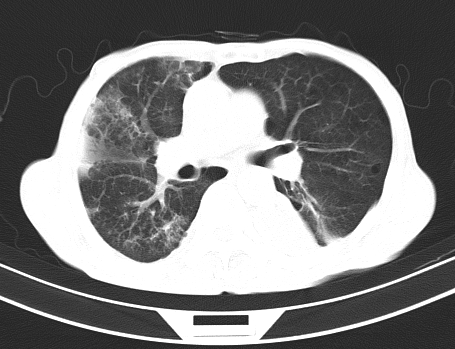

以下是引用gaoshengjiang在2008-5-30 19:53:00的发言:[br]右上叶可见大片实变影,其内可见充气支气管影及囊状影,右上叶尖端支气管走形区可见结节样影,左侧胸腔内可见胸腔胃影。纵隔淋巴结肿大。[br]考虑:1.右上肺阻塞性肺炎伴肺脓肿形成。支持转移所致。[br] 2.左侧胸腔胃。